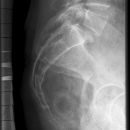

Lendenwirbelsäule lateral

Indikation

Fraktur und degenerative Veränderungen, Skoliose

Lagerung

exakte Seitenlage

Arme nach vorn oben,

Beine angewinkelt und 45° zwischen die Knie

evtl. einen 15° Keil unter Taille zum WS- Ausgleich

Zentralstrahl

ZS senkrecht auf Objekt- und Detektormitte

Quer: 2 QF über Beckenkamm

Längs: an QZ von den Dornfortsätzen 4 QF nach ventral

Bemerkung

möglichst bei Atemanhalten - Exspiration

auch im Stehen möglich (orthopädisch)

Qualitätskriterien

Rein seitliche Darstellung der Lendenwirbelsäule einschließlich ihrer Dornfortsätze mit 12. Brustwirbel und lumbosacralem Übergang.